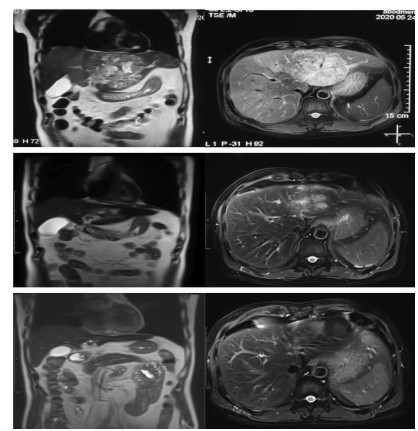

Differential diagnosis and treatment of jaundice after comprehensive treatment of advanced primary liver cancer: A case report

Si XIE, Ming YANG, Yuan HUANG, Lai WEI

2021, 37(2): 400-402. DOI: 10.3969/j.issn.1001-5256.2021.02.030

Abstract(841) HTML (375) PDF (2088KB)(58)

Abstract: